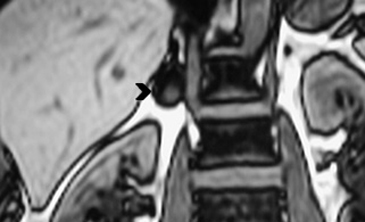

En TC sin contraste por lo general se observa una masa heterogénea, especialmente en caso de lesiones de mayor tamaño por la presencia de necrosis. Entre un 19 a 33% de los casos se identifican calcificaciones. Luego de la administración de contraste su refuerzo es heterogéneo y su patrón de lavado es consistente con una enfermedad maligna (Figura 22).

Los sitios más habituales de metástasis son hígado, pulmón, además de la invasión de las estructuras vasculares adyacentes, especialmente de la vena cava inferior, hallazgo que constituye una consideración fundamental al momento de planificar el abordaje quirúrgico (Figura 23 a y b).

Figura 23. Carcinoma suprarrenal derecho. Corte axial de resonancia magnética ponderado en T2 con saturación grasa (a) en que se demuestra una masa suprarrenal derecha con áreas hiperintensas en su espesor probablemente determinadas por necrosis (flecha) y corte coronal en secuencia TRUFISP (b) en que se observa un trombo tumoral que expande el lumen de la vena cava inferior (cabeza de flecha).Puede también presentar invasión directa de otras estructuras vecinas, como riñón, páncreas, bazo y diafragma.

En RM15 estas lesiones presentan intensidad de señal variable tanto en secuencias ponderadas en T1 como T2, dependiendo de la presencia de componentes necróticos y hemorrágicos, que como ya se mencionó es un hallazgo frecuente. Las áreas de necrosis suelen aparecer hipointensas en T1 e hiperintensas en T2, y las áreas de hemorragia si es en fase subaguda, vale decir aproximadamente una a siete semanas, se observara hiperintensidad de la lesión tanto en secuencia T1 y T2. En fase crónica (a partir de las 7 semanas en adelante) producto del deposito de hemosiderina y la presencia de una capsula fibrosa, las imágenes demuestran un anillo hipointenso tanto en secuencias T1 como T2. Con la administración de gadolinio ev se observa refuerzo de las porciones viables de tumor, con lo que se intensifica la señal.